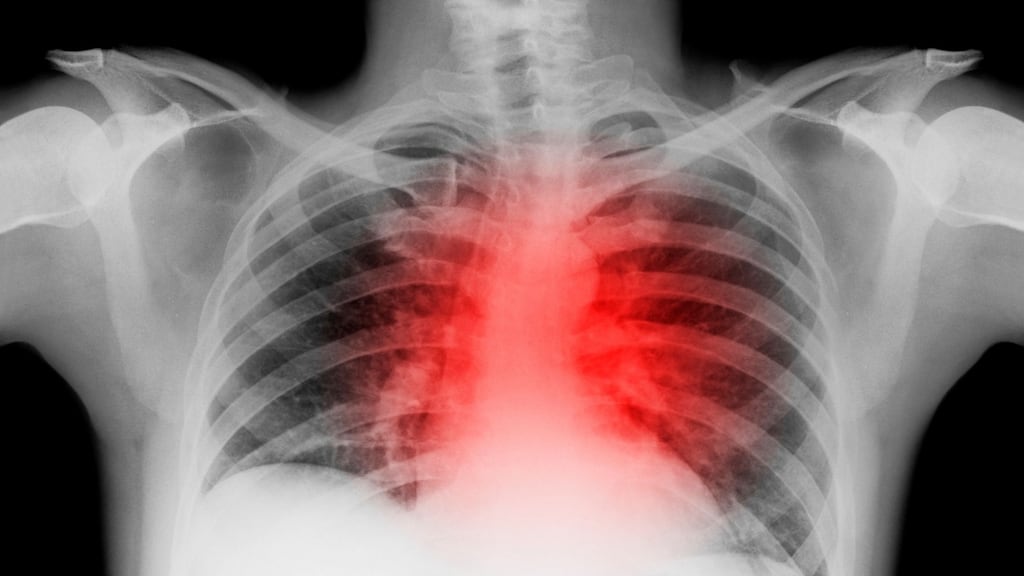

Seven serious cases involving cancer and other serious diseases were missed or misdiagnosed by a University Hospital Kerry radiologist, who has been placed on administrative leave since August.

Last night, the Tralee hospital said 20,171 of the 46,000 files produced by the consultant between March 2016 to July 2017 have so far been examined by a team of eight radiologists.

Besides the seven whose diseases were missed, 21 patients have been brought back for further tests because of concerns about original scans, but they have been given the all-clear.

The “look back” of all of the radiologist’s work now underway is one of the largest-ever to have been undertaken in this country, Gerard O’Callaghan of the HSE told a forum of public representatives in Tralee yesterday.

The radiologist was full-time with the Tralee hospital from March 2016 to July 2017, the meeting of Kerry TDs, councillors and health forum members was told.